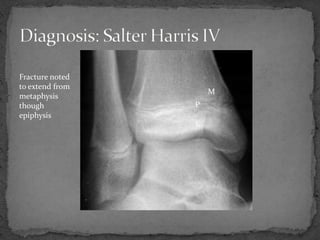

An 11-year-old male presented to the emergency department after being kicked by a cow, unable to bear weight on his right leg and experiencing excruciating pain. Examination revealed swelling and bruising around the right ankle with pain on movement. X-rays showed a fracture extending from the metaphysis through the epiphysis, classified as a Salter-Harris Type IV injury. This type of injury crosses the physis and involves both the epiphysis and metaphysis, is associated with a worse prognosis than other types, and may affect growth even with perfect reduction. Orthopedic consultation was recommended for possible open reduction and internal fixation if any displacement was present.